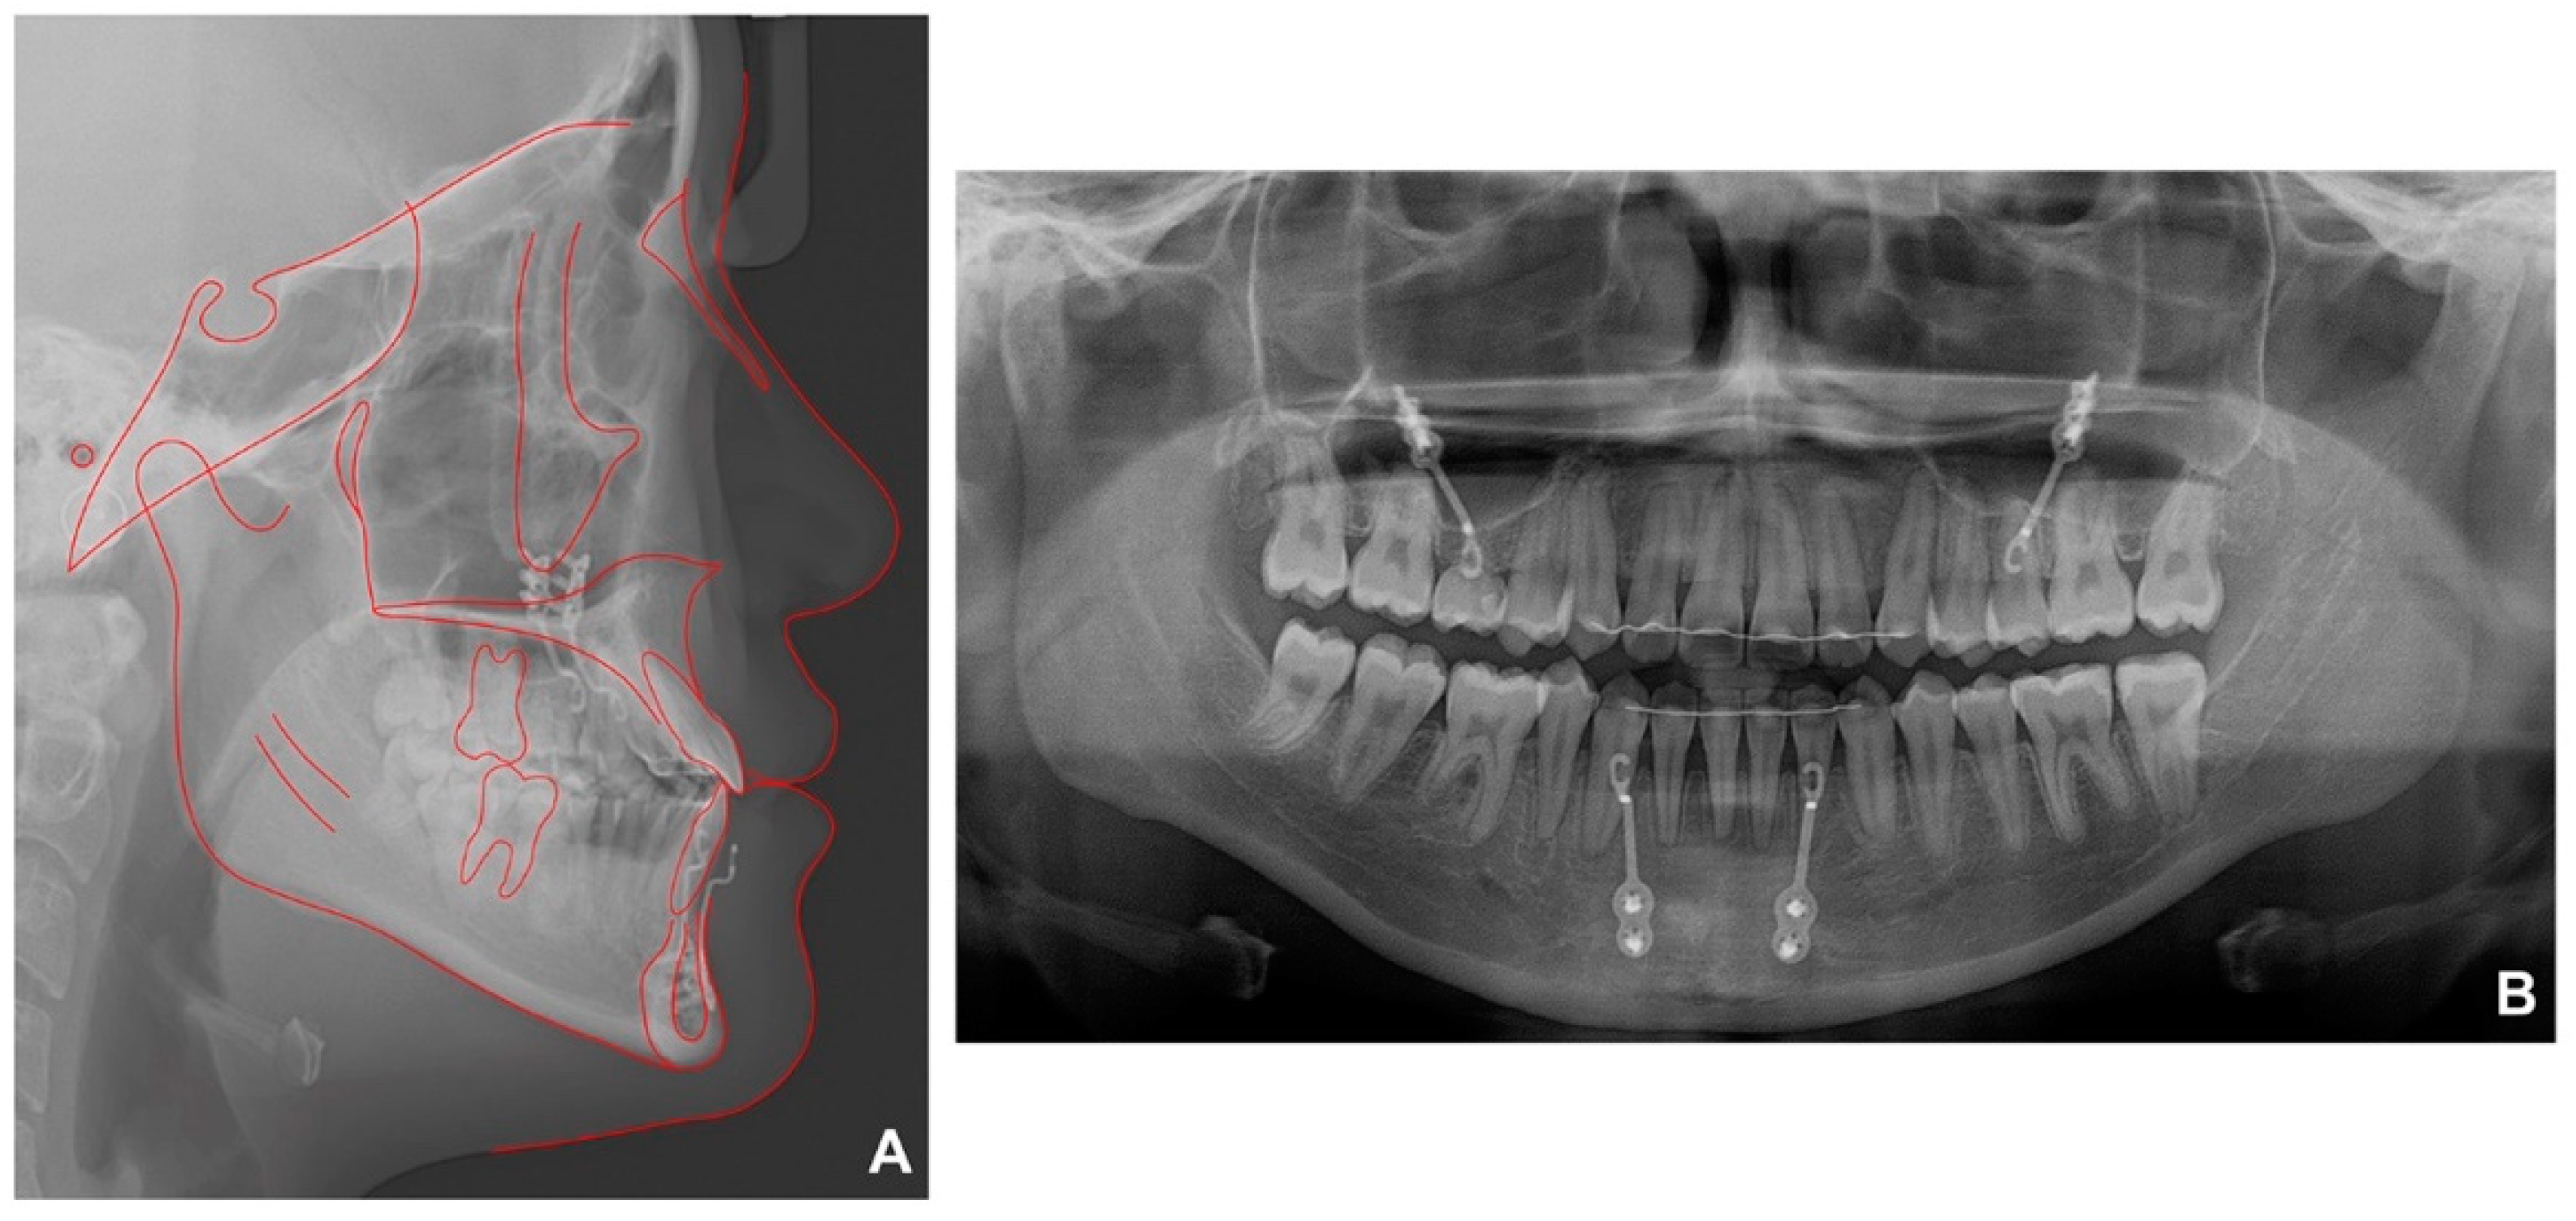

Lateral cephalometric analysis showed an SNA (angle formed by the lines connecting the sella, nasion, and point A) of 70.9°, an SNB angle of 72.7°, and an ANB angle of −1.9° (Table 1 and Figure 2A). Both the maxillary and mandibular incisors were lingually inclined, while the upper lip was retruded according to Ricketts’ esthetic line. The cervical vertebrae maturation index (CVMI) indicated that the patient was between stages 5 and 6 and had surpassed the maximum growth period. Panoramic radiography showed that the maxillary right second premolar was inversely impacted (Figure 2B) and the mandibular right second premolar was congenitally missing, with retained maxillary and mandibular primary second molars. Cone beam computed tomography (CBCT) was performed to determine the exact location of the maxillary right second premolar (Figure 2C,D). As shown in Figure 2C, it was clearly confirmed that the radiopacity of the maxillary sinus around the right impacted tooth was increased differently from that of the left maxillary sinus. Therefore, the reverse direction of the premolar towards the maxillary sinus caused perforation of the sinus wall, resulting in right sinusitis.

Figure 2. Pretreatment radiographs: (A) lateral cephalogram; (B) panoramic radiograph; (C,D) cone beam computed tomography.